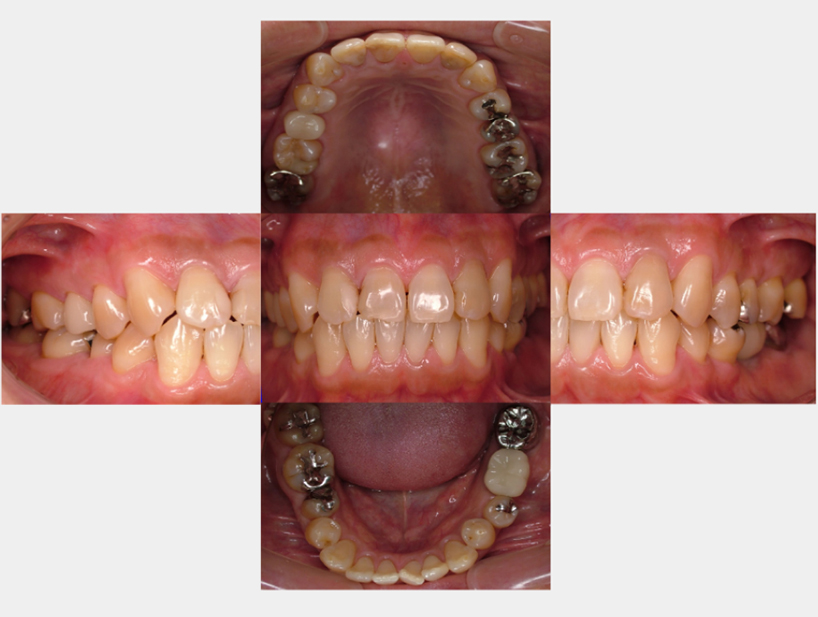

治療前治療後

| 治療内容 | インプラント奥歯1本・根管治療・矯正治療(圧下) |

|---|---|

| 患者様の年齢 | 40歳 |

| 患者様の性別 | 男性 |

| 治療期間 | 1年 |

| 治療回数 | 矯正治療合わせて50回程度 |

| 治療費用 | 根管治療1歯6万円/インプラント治療1歯50万円 矯正治療:1歯 10万円 |

| 治療で得られるメリット |

|

| 治療する際に起こる リスク・副作用 |